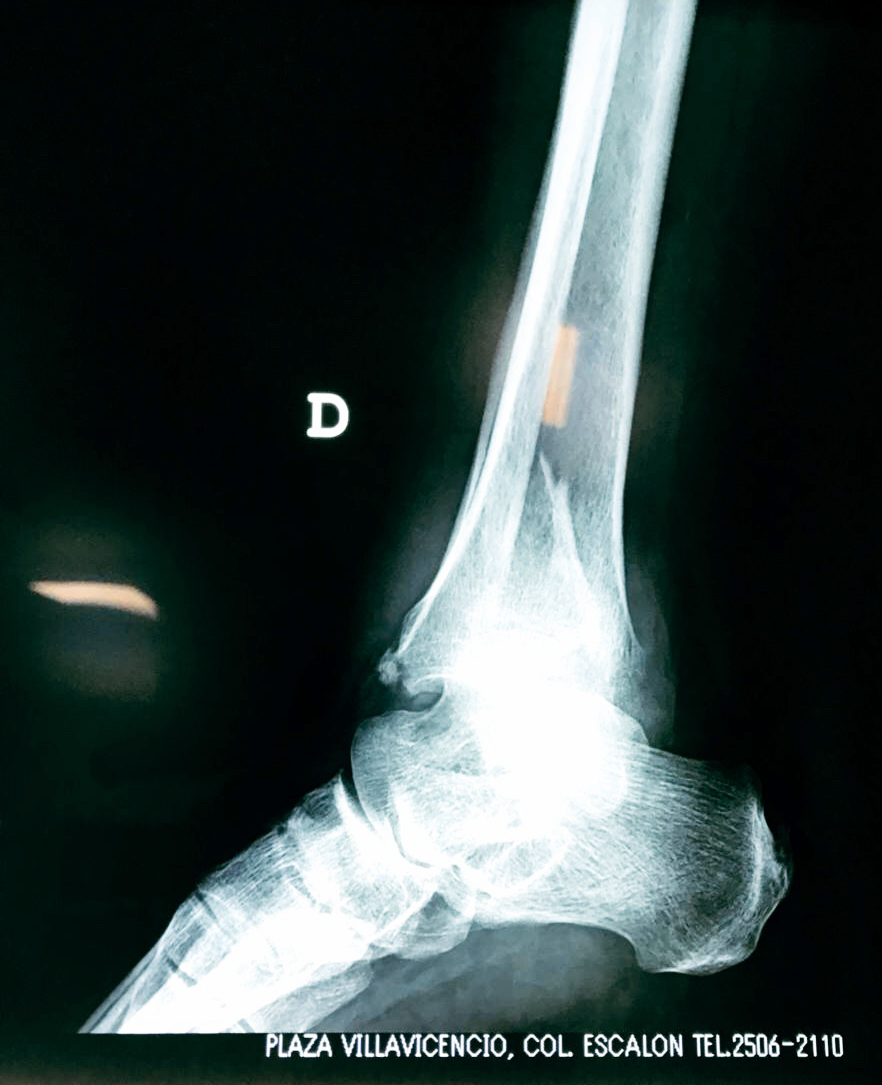

Algunas fracturas de tobillo pueden requerir cirugía si:

- Los extremos de los huesos están desalineados entre sí (desplazados).

- La fractura se extiende hasta la articulación del tobillo (fractura intra-articular).

- Los tendones o ligamentos (tejidos que sujetan los músculos y los huesos entre sí) están rotos.

Cuando se necesita cirugía, es probable que esta implique el uso de clavijas de metal, tornillos o placas para sostener los huesos en su lugar mientras la fractura se consolida. Los elementos de soporte pueden ser temporales o permanentes.